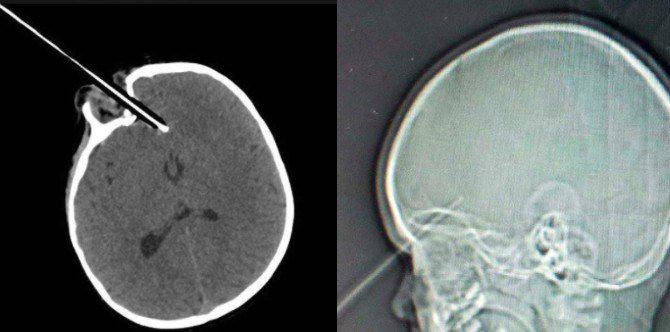

Saat itulah ia tersandung di tangga sambil memegang pensil. Seperti yang terlihat pada hasil foto sinar X, pensil tajam tersebut menikam matanya dan kemudian menembus sepanjang hampir 4 cm di bagian depan otaknya.

Untungnya, pensil yang tajam itu meleset beberapa milimeter dari bola matanya dan pembuluh darah besar. Dokter kagum betapa pensil itu melewati bola mata dan rongga mata.